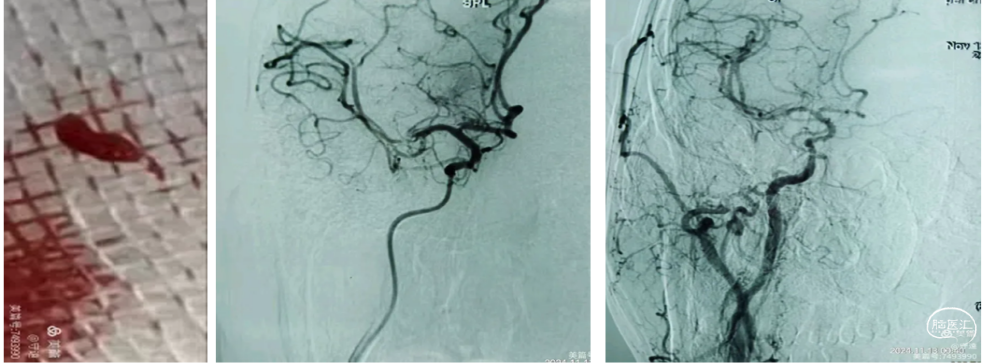

回撤5F中间导管于颈总动脉造影显示颈内动脉起始段重度狭窄。(下图1)

在C1段置入5mm保护伞,用3mm和4mm球囊扩张狭窄部位,但撤出球囊后狭窄略有改善。(下图2)

置入6~8~40mm自膨支架,支架位置良好,残余狭窄约30%。(下图3)

回撤导管与颈总动脉造影支架位置良好,远端大脑中动脉显影良好,分叉部无明确血栓征象。可能经替罗非班推注和血管通畅后逃逸的小血栓溶解了。再通后流动的血液就是最好的溶栓剂。